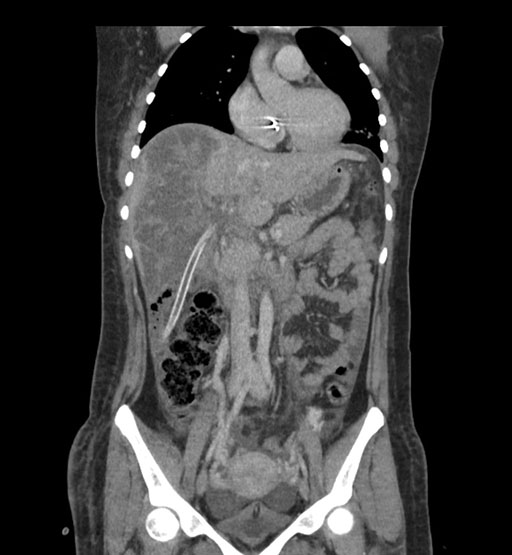

Coronal Arterial

Imaging analysis

Based on initial findings, which issue(s) would you be most concerned about?